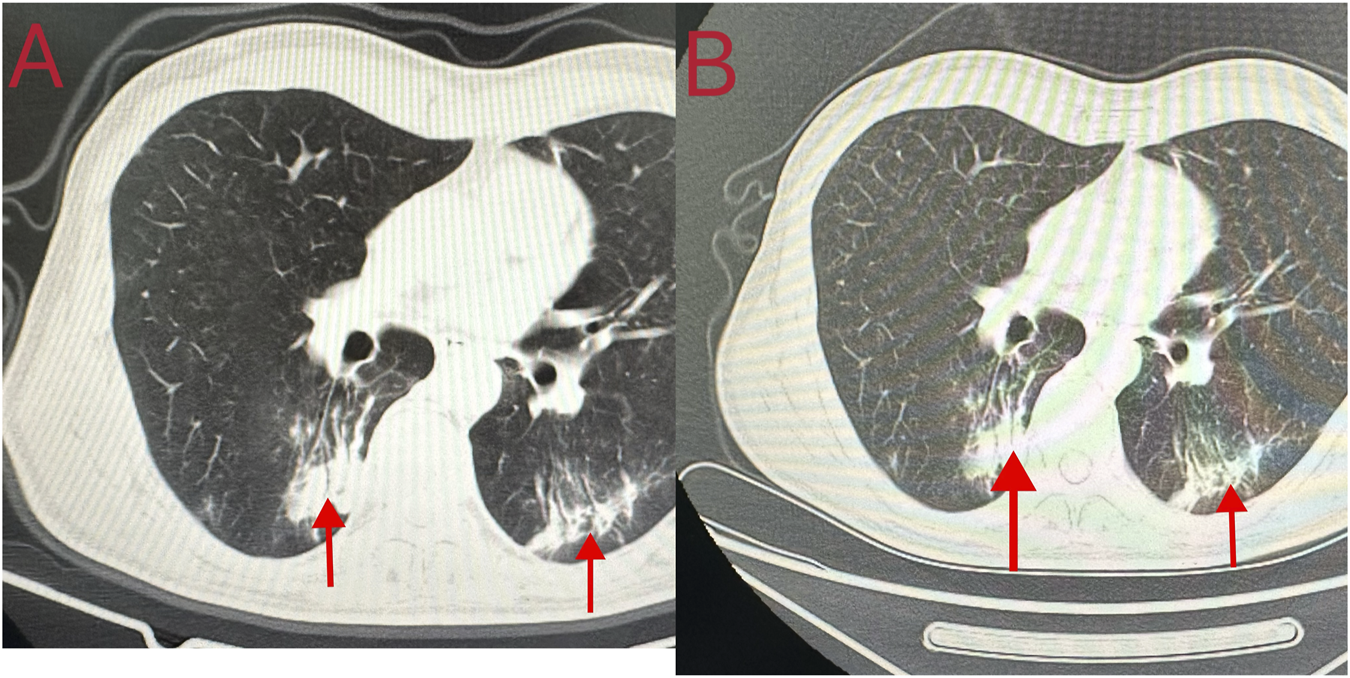

Cardiopulmonary resuscitation, oxygen inhalation, infusion, and other related treatments were urgently performed, and the patient was first sent to a local hospital for treatment. After admission, symptomatic treatments such as anti-infection, free radical scavenging, asthma relief, myocardial protection, anti-epilepsy, stomach protection, and fluid infusion were administered. After 2 days of hospitalization, he was transferred to our hospital for further diagnosis and treatment on the early morning of 18 October 2023. Physical examination on admission revealed a body temperature of 37.1°C, pulse rate of 92 beats/min, respiratory rate of 20 breaths/min, and blood pressure of 100/86 mmHg. He was intubated and placed on ventilator-assisted ventilation and was in a coma. The pupils were 4 mm in diameter and unresponsive to light. Bilateral breath sounds were coarse and no dry or wet rales were heard. The rhythm was normal and no pathological murmur was heard in any valve area. The abdomen was flat and soft, and the liver and spleen under the ribs were not palpable. Physiological reflex was absent and a pathological reflex was not elicited. Electrocardiogram examination at admission revealed the following: sinus rhythm, abnormal lower wall ST-T, possibly due to myocardial ischemia. Auxiliary test results were as follows: blood gas analysis: arterial partial pressure of oxygen 201.5 mmHg; arterial partial pressure of carbon dioxide 49.3 mmHg; white blood cell count 16.23 × 109/L (3.5–9.5 × 109/L), neutrophil ratio 89% (40%–75%); and platelet count 121 × 109/L (125–350 × 109/L). Laboratory blood test results were as follows: alanine aminotransferase 48 U/L (9–50 U/L), aspartate aminotransferase 60 U/L (15–40 U/L), serum myoglobin 114 ng/mL (0–70 ng/mL), creatine kinase isoenzyme 7.10 ng/mL (0.3–4 ng/mL), serum high-sensitivity troponin I 170.85 (<17.5 ng/L), N-terminal pro-brain natriuretic peptide 1,387 pg/mL (emergency ≤300 pg/mL), interleukin-6 63.50 pg/mL (0–7 pg/mL), and interleukin-1b 6.15 pg/mL (0–5 pg/mL). Brain CT and magnetic resonance imaging showed no apparent abnormalities. Chest CT revealed double pneumonia, bilateral pleural effusion, multiple fractures of the left 1st to 6th ribs, fractures of the right 2nd and 3rd ribs, severe respiratory artifacts (Figure 2), and left pneumothorax (Figure 3). The admission diagnoses were acute dichloromethane poisoning, hemopneumothorax, and rib fracture. After admission, the patient was actively treated with anti-infection therapy, reduce organ edema, glucocorticoids, ventilator-assisted respiration, chest strap fixation, and nutritional support. On the 7th day after admission, the patient’s blood test results revealed a decrease in white blood cell count 11.37 × 109/L (3.5–9.5 × 109/L) and neutrophil ratio 80.1% (40%–75%), and increased levels of alanine aminotransferase 206 U/L (9–50 U/L) and aspartate aminotransferase 84 U/L (15–40 U/L). On the 14th day of admission, routine blood, liver, and kidney function tests showed no obvious abnormalities, and the tracheal tube was removed. On the 29th day of admission, electromyography showed lesions of the right median nerve in the wrist and lesions of the right superficial peroneal nerve. The electroencephalogram showed no abnormalities. After 35 days of treatment, the patient’s condition improved and he was discharged. On 26 December 2023, the patient complained of chest pain and underwent a reexamination. Chest CT showed a high-density shadow in the lungs (Figure 4). After 9 days of comprehensive anti-infection treatment, the patient’s condition improved, and he was discharged. Follow-up after discharge indicated the absence of sequelae. The patient was transferred from his original job and engaged in other work.

FIGURE 4

Chest computed tomography findings of the patient during the second adimission. (A, B) A high-density shadow in the lungs.